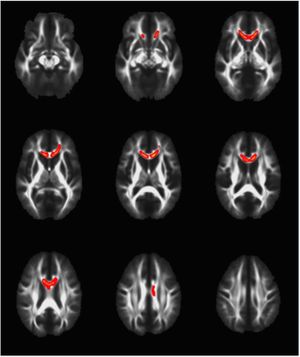

Publication: PLoS One. 2015 Dec 4;10(12):e0143208. PMID: 26636762 | PDF Authors: Cramer CK, Yoon SW, Reinsvold M, Joo KM, Norris H, Hood RC, Adamson JD, Klein RC, Kirsch DG, Oldham M. Institution: Department of Radiation Oncology, Duke University Medical Center, Durham, NC, USA. Background/Purpose: Despite the clinical benefit of whole brain radiotherapy (WBRT), patients and physicians are concerned by the long-term impact on cognitive functioning. Many studies investigating the molecular and cellular impact of WBRT have used rodent models. However, there has not been a rodent protocol comparable to the recently reported Radiation Therapy Oncology Group (RTOG) protocol for WBRT with hippocampal avoidance (HA) which is intended to spare cognitive function. The aim of this study was to develop a hippocampal-sparing WBRT protocol in Wistar rats. Methods: The technical and clinical challenges encountered in hippocampal sparing during rat WBRT are substantial. Three key challenges were identified: hippocampal localization, treatment planning, and treatment localization. Hippocampal localization was achieved with sophisticated imaging techniques requiring deformable registration of a rat MRI atlas with a high resolution MRI followed by fusion via rigid registration to a CBCT. Treatment planning employed a Monte Carlo dose calculation in SmART-Plan and creation of 0.5 cm thick lead blocks custom-shaped to match DRR projections. Treatment localization necessitated the on-board image-guidance capability of the XRAD C225Cx micro-CT/micro-irradiator (Precision X-Ray). Treatment was accomplished with opposed lateral fields with 225 KVp X-rays at a current of 13mA filtered through 0.3 mm of copper using a 40x40 mm square collimator and the lead blocks. A single fraction of 4Gy was delivered (2Gy per lateral field) with a 41 second beam on time per field at a dose rate of 304.5 cGy/min. Dosimetric verification of hippocampal sparing was performed using radiochromic film. In vivo verification of HA was performed after delivery of a single 4Gy fraction either with or without HA using γ-H2Ax staining of tissue sections from the brain to quantify the amount of DNA damage in rats treated with HA, WBRT, or sham-irradiated (negative controls). Results: The mean dose delivered to radiochromic film beneath the hippocampal block was 0.52Gy compared to 3.93Gy without the block, indicating an 87% reduction in the dose delivered to the hippocampus. This difference was consistent with doses predicted by Monte Carlo dose calculation. The Dose Volume Histogram (DVH) generated via Monte Carlo simulation showed an underdosage of the target volume (brain minus hippocampus) with 50% of the target volume receiving 100% of the prescription isodose as a result of the lateral blocking techniques sparing some midline thalamic and subcortical tissue. Staining of brain sections with anti-phospho-Histone H2A.X (reflecting double-strand DNA breaks) demonstrated that this treatment protocol limited radiation dose to the hippocampus in vivo. The mean signal intensity from γ-H2Ax staining in the cortex was not significantly different from the signal intensity in the cortex of rats treated with WBRT (5.40 v. 5.75, P = 0.32). In contrast, the signal intensity in the hippocampus of rats treated with HA was significantly lower than rats treated with WBRT (4.55 v. 6.93, P = 0.012). Conclusion: Despite the challenges of planning conformal treatments for small volumes in rodents, our dosimetric and in vivo data show that WBRT with HA is feasible in rats. This study provides a useful platform for further application and refinement of the technique. Funding:

MRI with labeled structures from atlas registered to the CBCT. Registration was carried out with the open source imaging tool 3D Slicer, Version 4.4.0. |